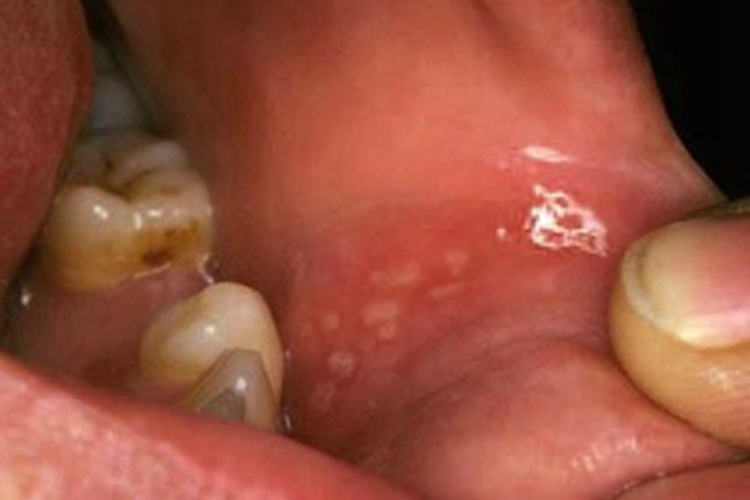

创伤性溃疡可表现为唇内侧出现一卵圆形溃疡,境界清楚,溃疡底发白,周边轻度炎性潮红。

创伤性溃疡可导致唇内侧的黏膜破损,之后可形成溃疡或糜烂面,开始时可能仅有轻微疼痛或肿胀,溃疡为形态不整的卵圆形,且分界清楚,有角的黏膜缺损,因唾液的浸渍,可使溃疡底发白,周边轻度炎性潮红,自觉疼痛。此外,表面渗出液和唾液混在一起,发生溃疡后可影响进食。